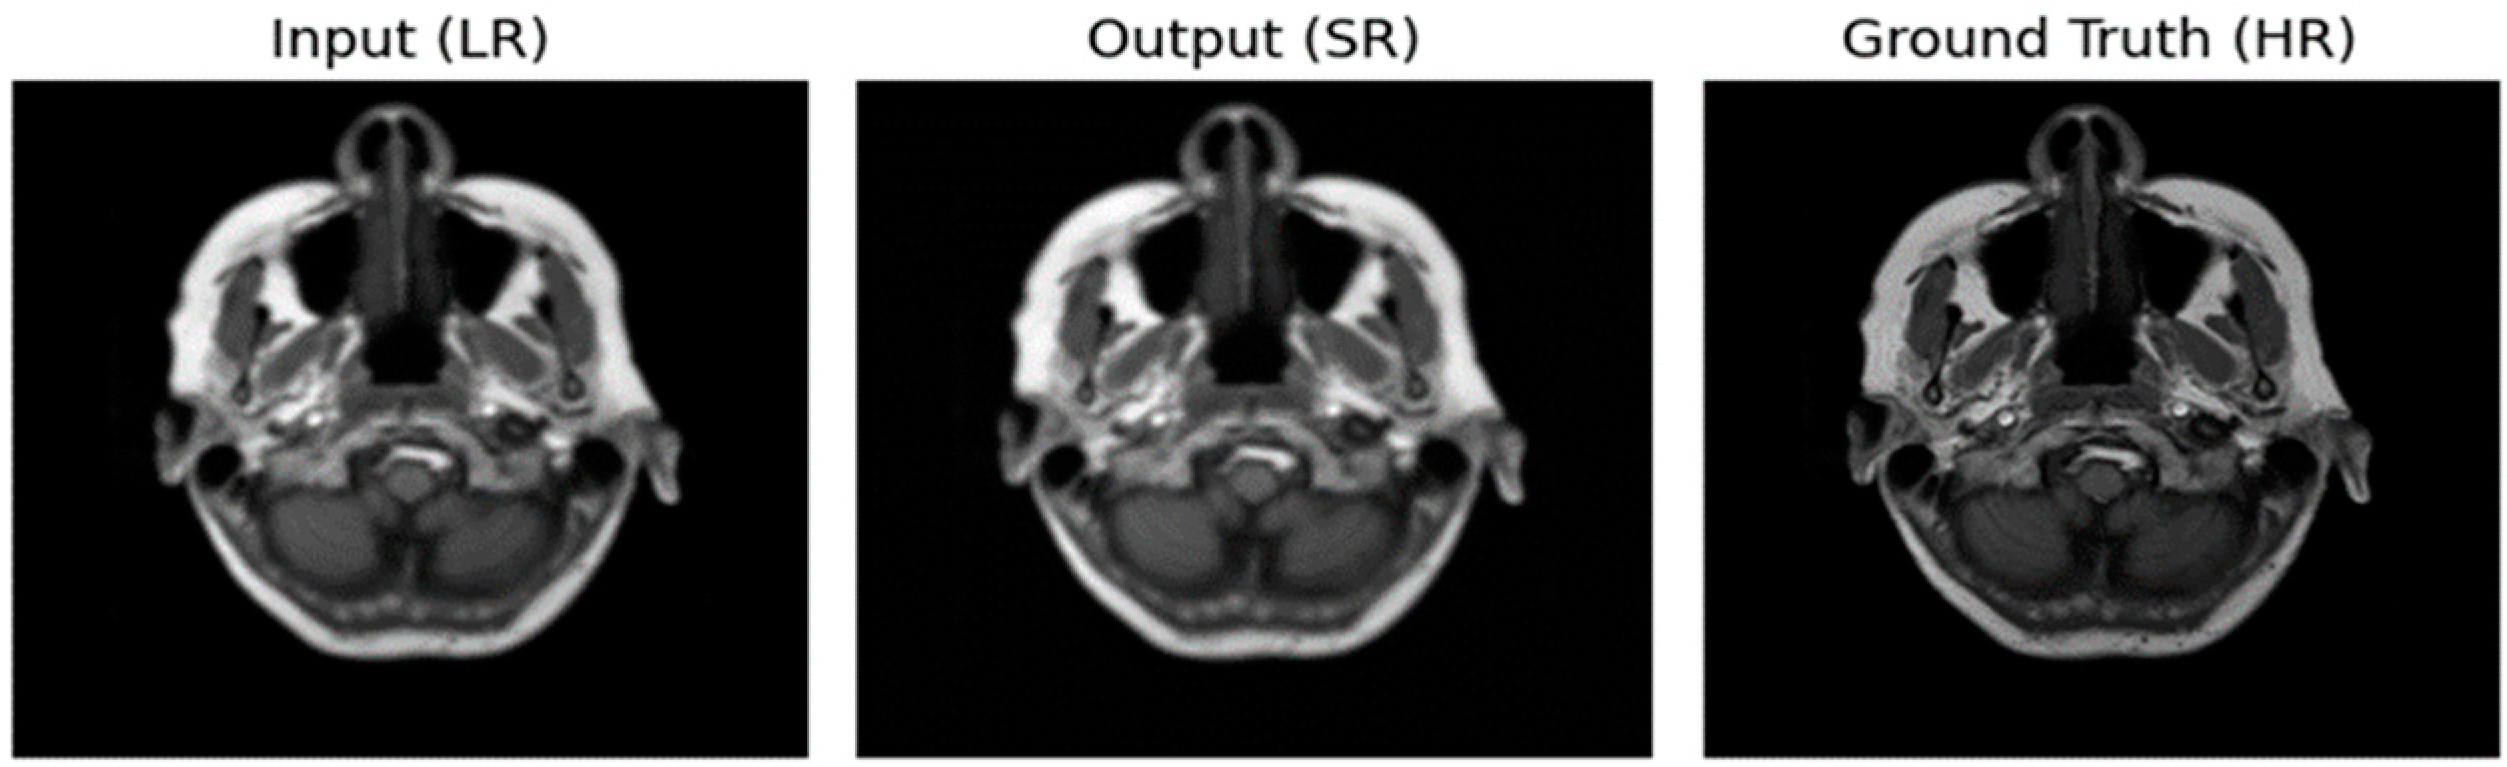

3.2. Performance of ADAM Optimizer and Use of Loss Functions Using Super Resolution Convolution Neural Network (SRCNN)

3.3. Performance of ADAM Optimizer and Use of Loss Functions Using Super Resolution Residual Network (SR ResNet)

3.4. Comparative Analysis Table of SRCNN and SR ResNet with ADAM Optimizer and Loss Functions